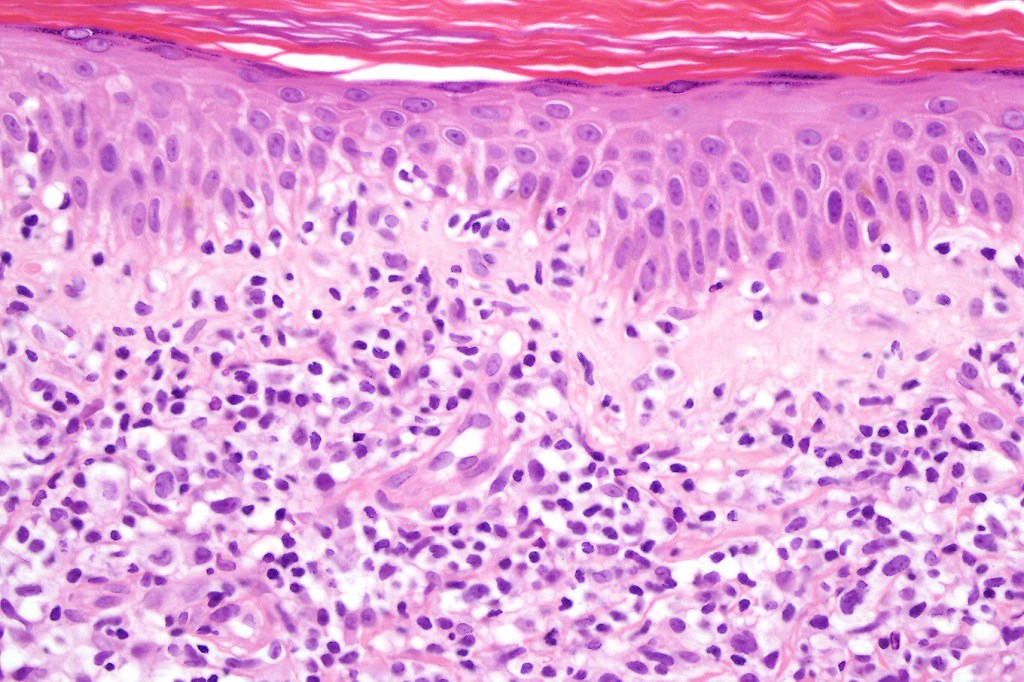

Histological features

The histological hallmark of mycosis fungoides is the presence of large atypical lymphocytes with a convoluted/cerebriform nuclear border (Sézary cells). These may be found at the epidermal-dermal jnuction and as collections within the epidermis (Pautrier microabscess). These are most easily found in plaque stage disease. The epidermal component can be subtle in patch stage disease and is often lost in tumor stage dsease. The classification into patch, plaque & tumor stage disease is less helpful histologically as the features merge from one to the other. It is all a matter of degree.

Patch stage disease

•Changes can be subtle & dependent on clinicopathological correlation; in many patients sequential biopsies over many months may be necessary to establish the diagnosis.

•Mild hyperkeratosis & focal parakeratosis, acanthosis, epidermal atrophy or of normal thickness

•Superficial dermal lymphocytic infiltrate containing variable numbers of Sézary cells with atypical, irregular, hyperchromatic nuclei surrounded by a halo; these can be very few in number and dependant on viewing multiple levels

•Palisading of atypical lymphocytes along the epidermal-dermal border

•Pautrier microabscesses may be present but are often absent in patch stage disease

•Variable interface change with keratinocyte necrosis & pigmentary incontinence

•Eosinophils & plasma cells sometimes present

•Coarse collagen bundles in the papillary dermis can be a feature but this is not as marked as seen in plaque disease

.Although in typical mycosis fungoides fungoides, spongiosis is absent, exceptionally it can be a feature

Plaque Stage Disease

•Compact hyperkeratosis & patchy parakeratosis

•Acanthosis

•Psoriasiform hyperplasia common

•Epidermotropism is often marked with conspicuous Pautrier microabscesses